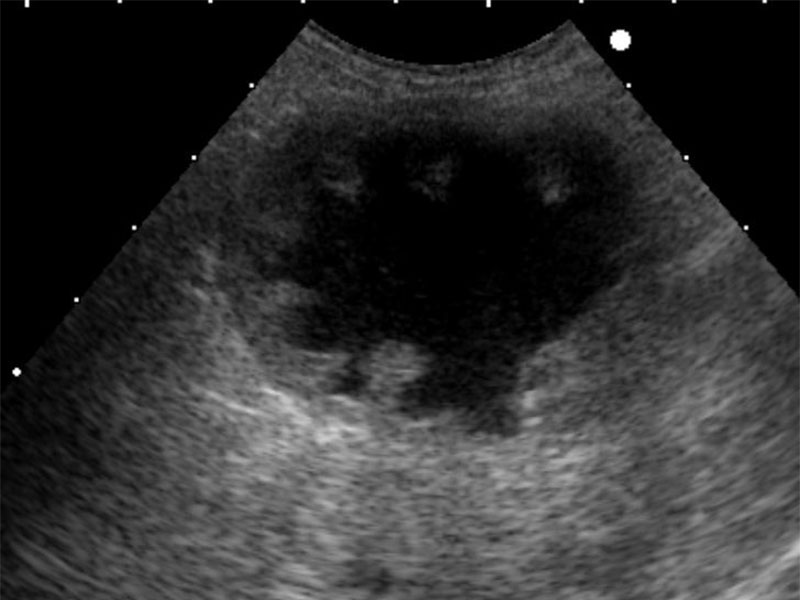

脾臓

● 検査

超音波

● 疾患

がん、脾腫

間質肉腫(犬、紹介先の病院で摘出手術)

肥満細胞腫(猫、当院で摘出手術)

骨髄脂肪腫(犬、良性)

脾臓の疾患は、レントゲン検査や血液検査では診断できず、超音波(エコー)検査が基本になります。